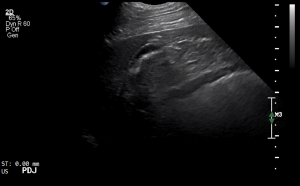

SIMON Ultrasound Database

This ultrasound database is a free resource for students and doctors!

Our collection includes videos of dogs, cats, horses, cows, humans, and many other species!

–Canine and Feline abdominal ultrasound videos were generously provided by the Cummings School of Veterinary Medicine at Tufts University.